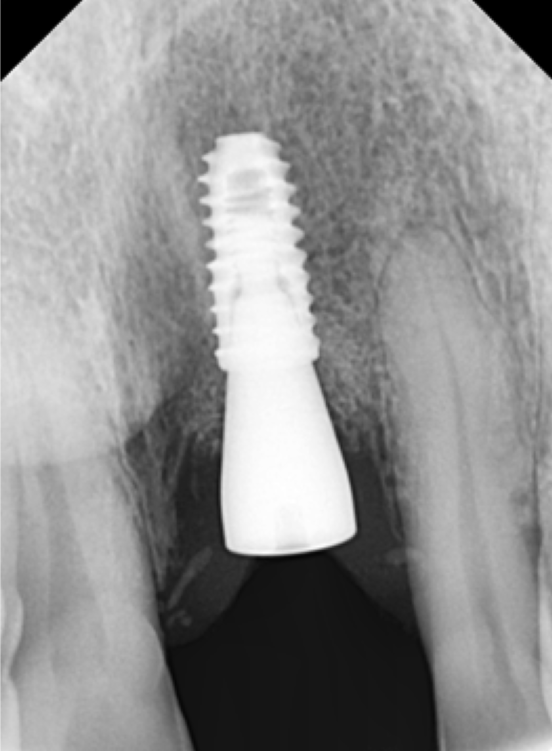

앞니 수술을 하기 위해서 3차원 CT 엑스레이 촬영을 했습니다.

CT 사진을 보며 적당한 위치를 선정하고, 임플란트의 길이와 두께를 정합니다.

뼈이식을 추가로 진행하였으며, 3개월 후에 보철을 올리기로 했습니다.

위에 앞니 임플란트를 심은 지 1달이 지났습니다.

한달까지가 임플란트와 치조골 뼈의 골유착에 가장 중요한 시기입니다.

앞니만 자세히 볼 수 있는 치근단 엑스레이를 찍어서

임플란트의 상태를 확인합니다.

임플란트와 뼈의 유착관계가 좋습니다. 뼈도 잘 차고 있습니다. ^^

두달만 더 기다리기로 합니다.